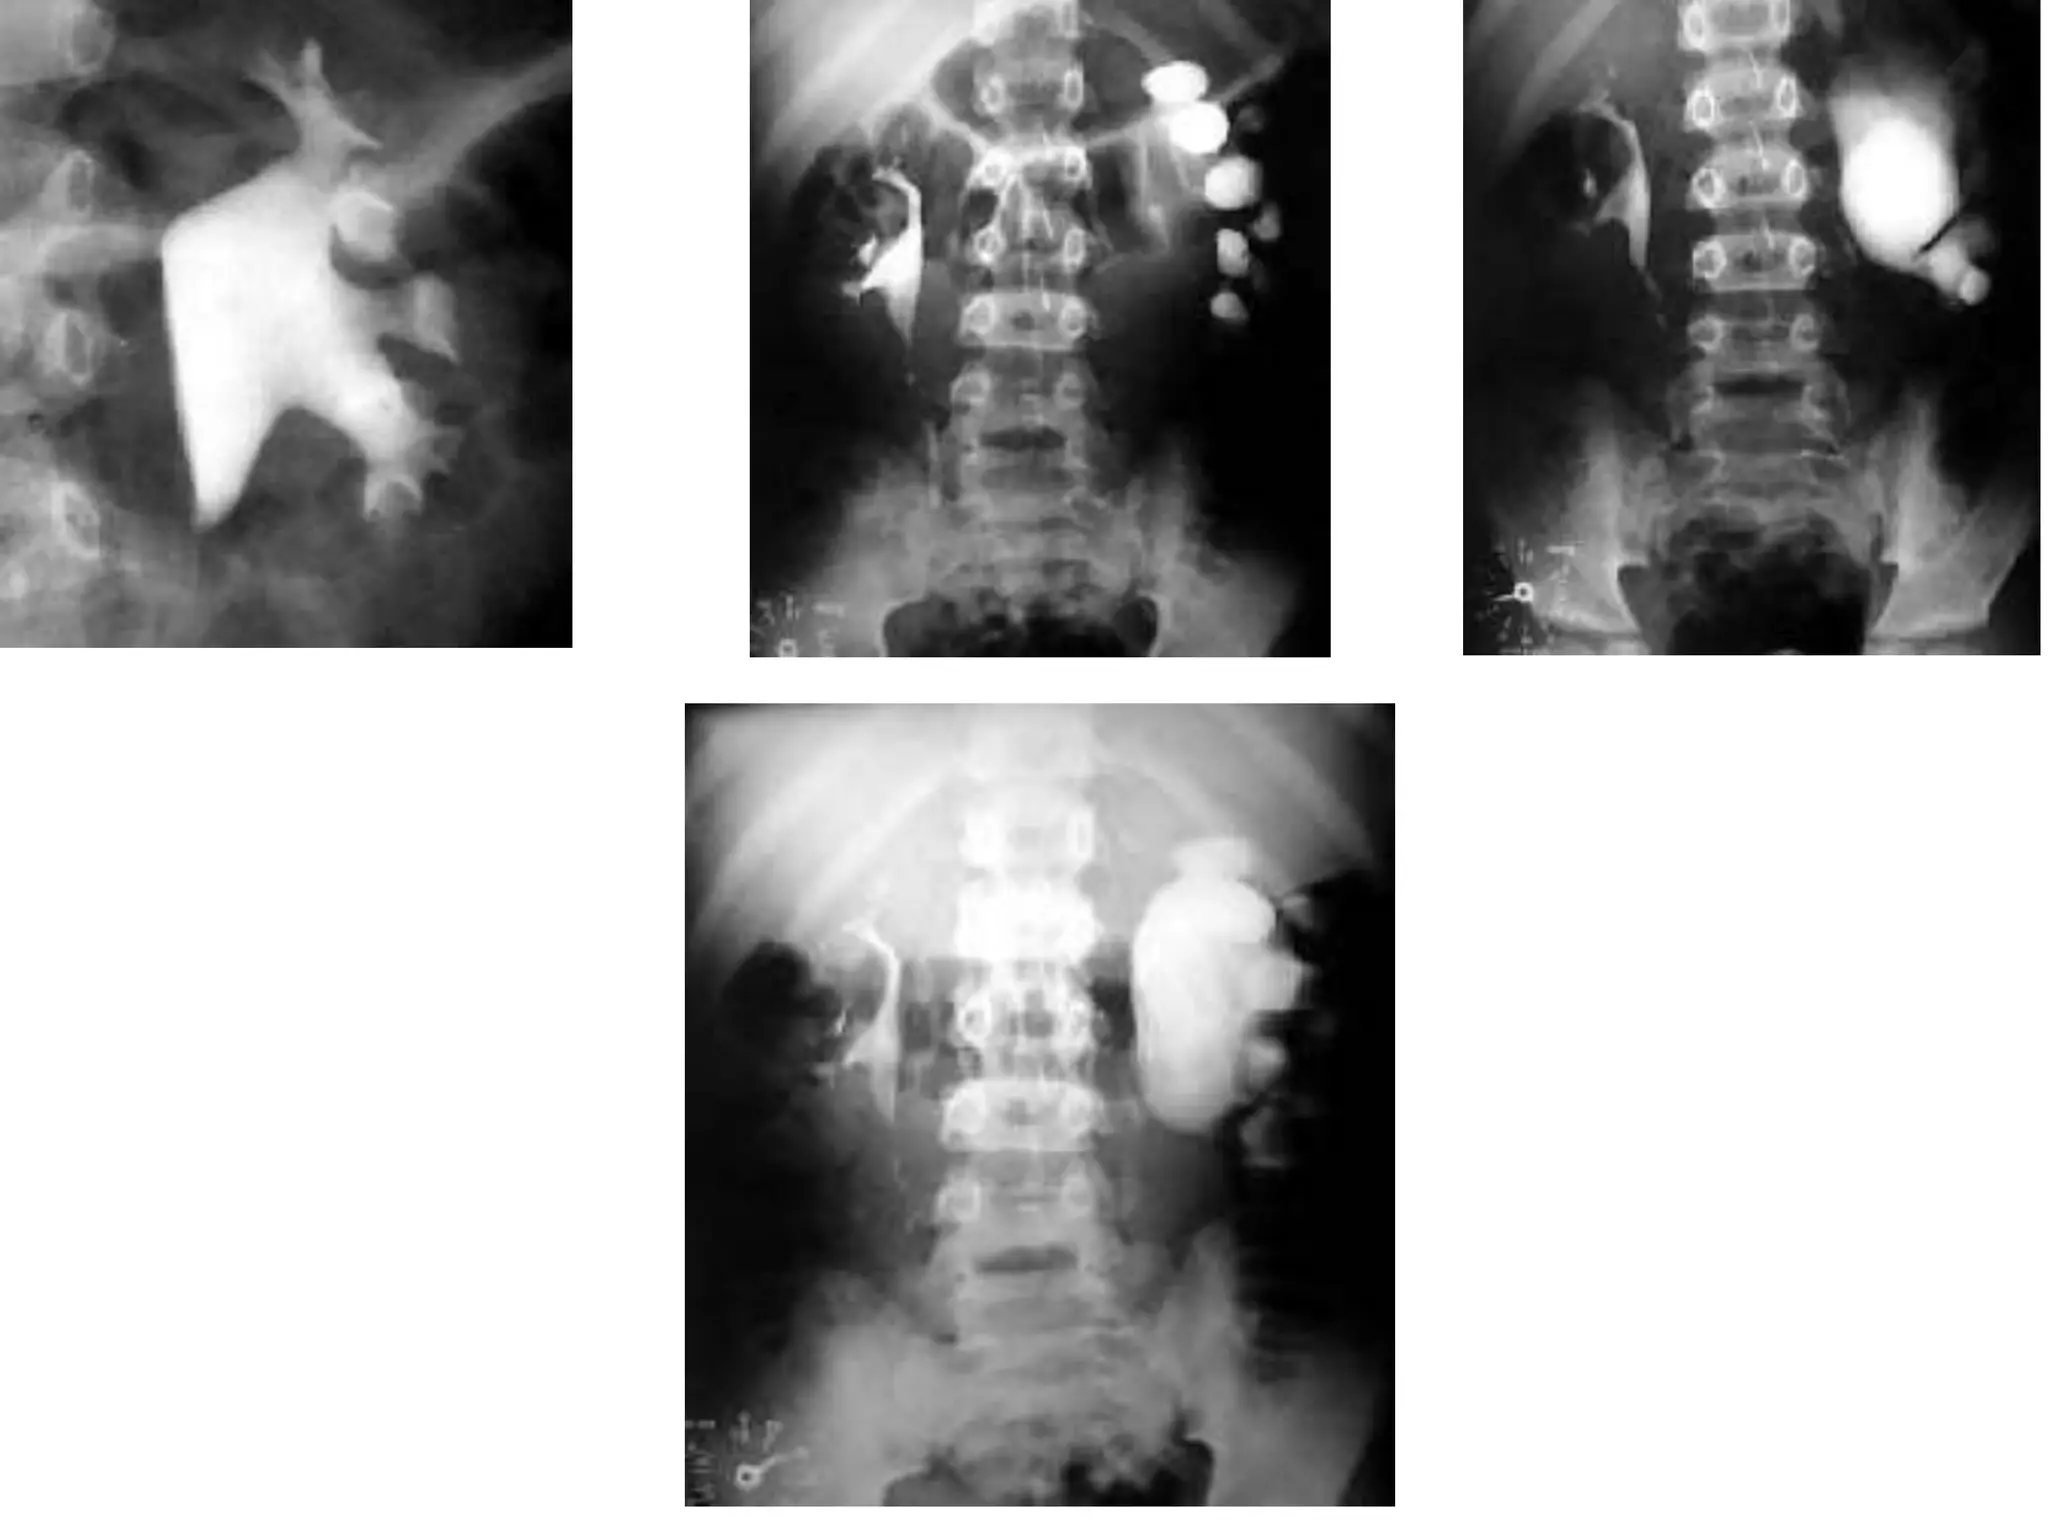

Clasificacion de la hidronefrosis

Grado 0: Riñón normal sin hidronefrosis

Grado 1: Pelvis renal ligeramente dilatada sin ectasia calicial

Grado 2: Pelvis renal moderadamente dilatada con ectasia calicial leve

Grado 3: Pelvis renal grande, cálices dilatados y parénquima normal

Grado 4: Pelvis renal muy grande, cálices grandes y dilatados

y adelgazamiento del parénquima renal.

Clasificacion de lahidronefrosis Grado 0: Riñón normal sin hidronefrosis Grado 1: Pelvis renal ligeramente dilatada sin ectasia calicial Grado 2: Pelvis renal moderadamente dilatada con ectasia calicial leve Grado 3: Pelvis renal grande, cálices dilatados y parénquima normal Grado 4: Pelvis renal muy grande, cálices grandes y dilatados y adelgazamiento del parénquima renal. • CLINICAS UROLOGICAS, MADRID ES.